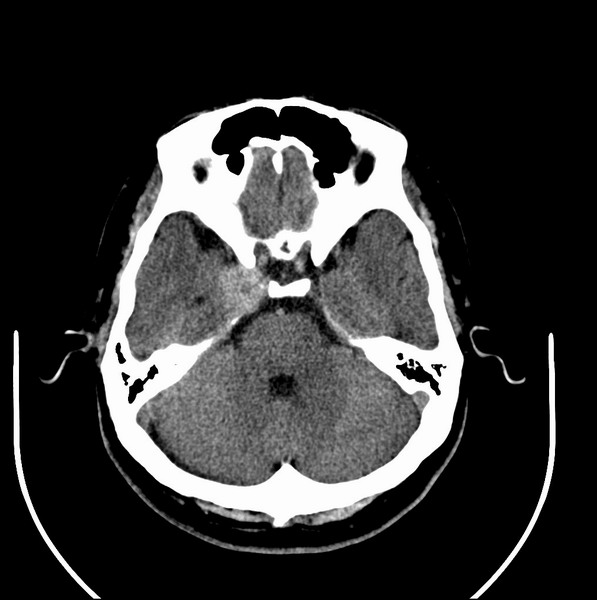

扫描示鼻咽腔不对称,中度狭窄,右侧咽隐窝消失,局部软组织肿块,鼻咽右侧壁增厚形成肿块,突入鼻咽腔,肿块平扫呈等密度,肿块向深部侵润,右侧翼内外肌受侵,右侧咽旁间隙变窄;向后生长,头长肌界线欠清,向后上生长侵犯同侧颈动脉鞘区。双侧海绵窦增宽,内见软组织影与鼻咽部肿块相连。考虑鼻咽癌。鼻咽癌主要是放射治疗,且效果较好;到当地有治疗设备较大医院治疗即可。

这个病例有点特殊,和常见的鼻咽癌不太一样,以向颅内侵犯为主,骨质破坏区小。鼻咽癌首先要考虑,有没有其他可能?本人不会看mr片,期待有人能讲解,期待病理。

鼻咽部新生物(纤维血管瘤?鼻咽癌?)侵犯右侧中颅窝底及右侧海绵窦;建议必要时活检定性。